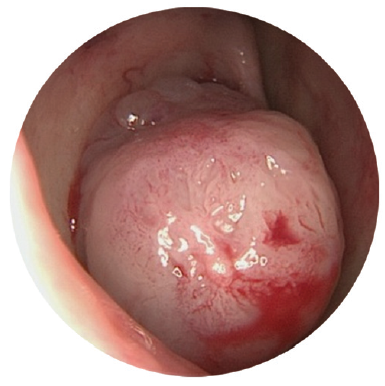

Our observations of patients in the postoperative period reliably showed that 11 (10.6%) out of 103 patients of group I who were examined, and 4 (3.9%) of those in group II had repeated persistent lacrimation in the period from 1–6 months. The causes of repeated development of lacrimation included the development of granulation tissue in the area of the dacryostoma (Fig. 7) for 2 (1.9%) patients in group I and 3 (2.9%) patients in group II; the formation of synechiae (Fig. 8) for 9 (8.7%) patients on group I and 1 (0.9%) patient in group II.

Fig. 7. Patient K., 38 years old. Endoscopy of the nasal cavity. Granulation in the area of dacryorhinostomy 1 month after endoscopic endonasal dacryocystorhinostomy